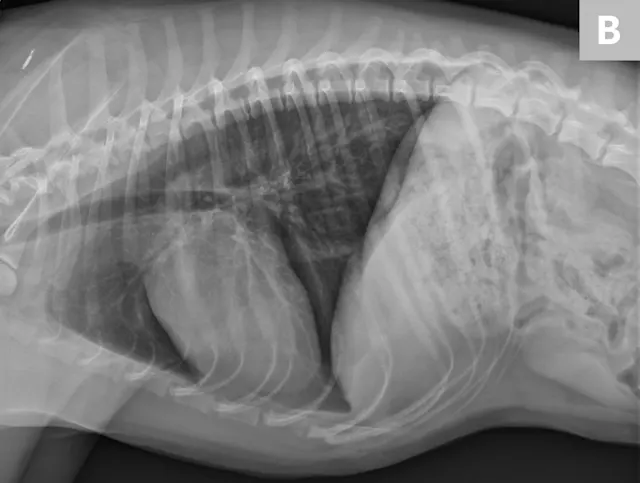

Figure 1 Ventrodorsal view obtained while holding the patient’s thoracic limbs with the hands

Images courtesy of Janet Paquette, AS, LVMT